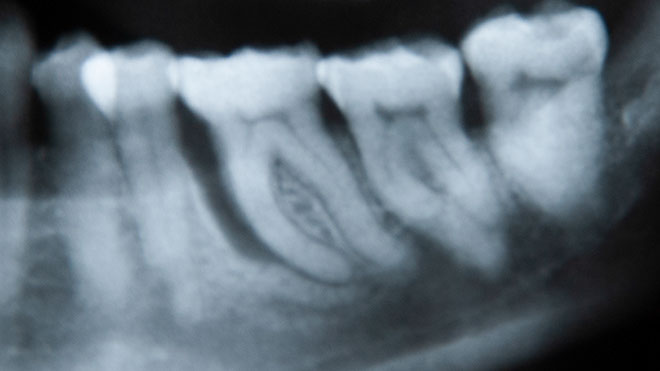

• OPG (Orthopantomogram - X-ray overview)